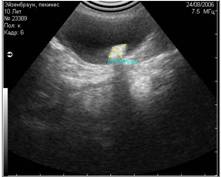

Рис. 18. Артефакт периферического эхоакустического усиления . Звуковая волна слева практически не ослабляется, проходя через наполненный жидкостью пузырь, поэтому область позади него остаётся яркой. Звуковая волна справа, проходящая через паренхиму, ослабляется и затухает. |

Рис. 19. Артефакт периферического усиления, возникший позади желчного пузыря. |